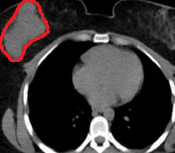

CT θώρακα. Παρουσία μεγάλης, ακανόνιστης μάζας στο δεξιό μαστό (Ευγενική παραχώρηση Dr. V. Penopoulos)